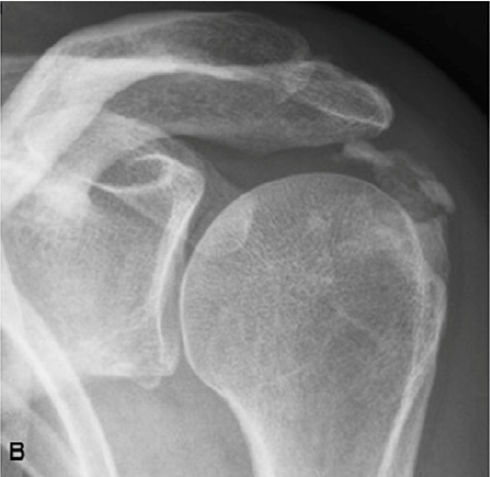

Ακτινολογική ταξινόμηση της ασβεστοποίησης στον ώμο (Gartner and Hayer)

Ανάλογα με την απεικόνιση στην ακτινογραφία ταξινομείτε ως εξής:

| Τύπος Ι : Ομαλά όρια, αυξημένη πυκνότητα ασβέστωσης. Φάση σχηματισμού | Τύπος ΙΙ: Σχήμα ομαλό, πυκνό ή οξύ, περιοχές ακτινοδιαπερατές. Φάση σταθεροποποίησης | Τύπος ΙΙΙ: Διάφανη, νεφελώδης εμφάνιση, χωρίς σαφή όρια. Φάση απορρόφησης |